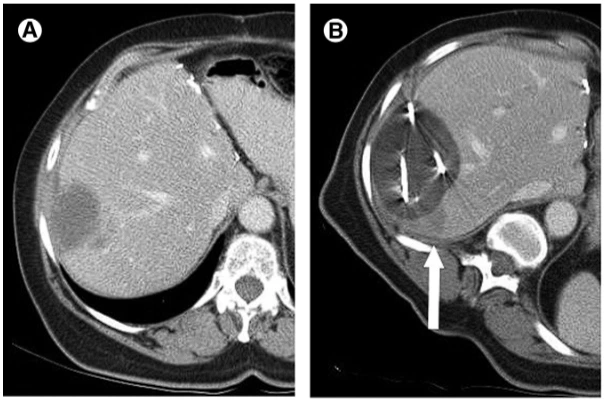

通过-140℃极冷冻结和+45℃快速复温的交替循环,在微创条件下精准杀灭肿瘤细胞,保护周围健康组织。

实时影像监测冰球范围,精确控制治疗区域,最大程度保护正常组织和重要器官

氩氦刀冷冻消融的免疫增强效应

这种“冷冻-免疫”协同效应使氩氦刀不仅是局部物理治疗手段,还可能转化为全身性免疫治疗,对晚期肿瘤和转移性病变具有潜在价值。 相对于其他微创手段,冷冻消融对蛋白质结构影响最低,因此释放的抗原能更精准地激活免疫系统(Cryoablation plus sintilimab and lenvatinib in advanced or metastatic intrahepatic cholangio carcinoma: a phase2 trial)。